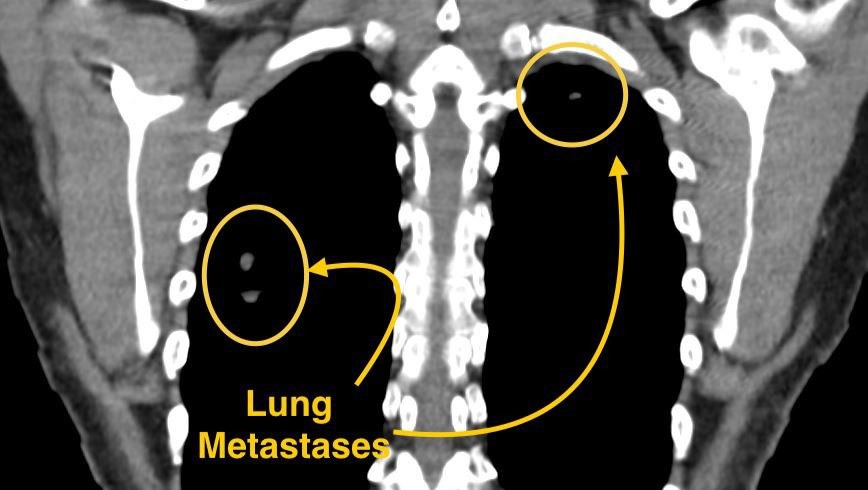

Our mom is only 51 years old, but right now, she’s fighting for her life. She has been diagnosed with advanced cervical cancer that has already spread beyond her uterus into her bladder, rectum, and even her lungs. Every single day has been a battle against pain, fear, and uncertainty and yet she keeps smiling, trying to protect us from her suffering.

Dr. Arguello believes this surgery is the only realistic way to save her life; the treatment cannot overcome that amount of cancer. The surgery would reduce the tumor burden by 90% in a matter of hours.